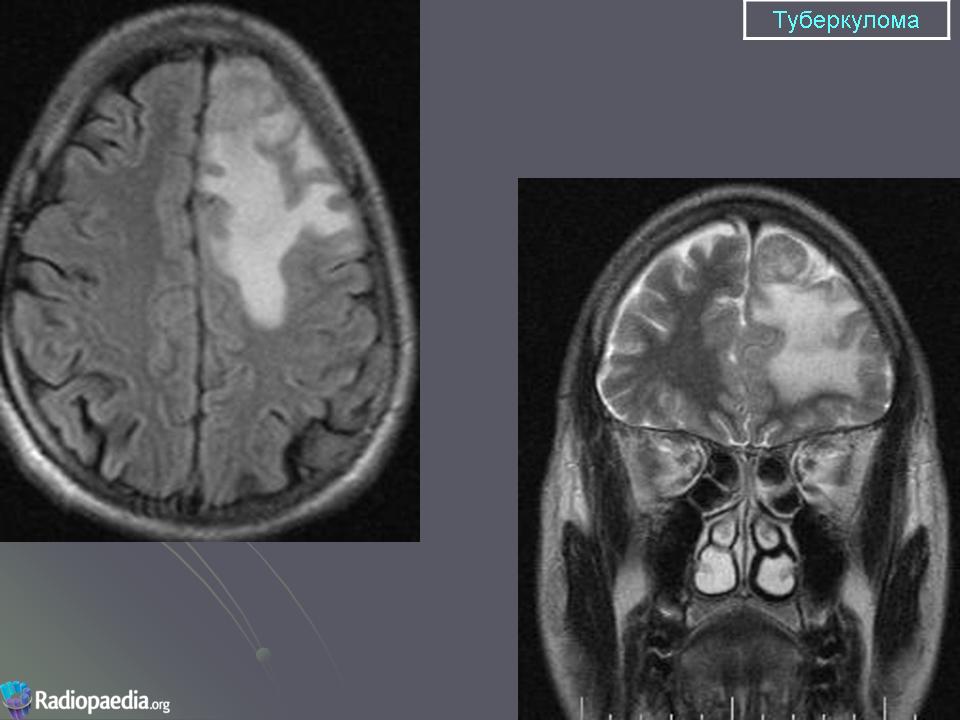

Туберкулёз ЦНС